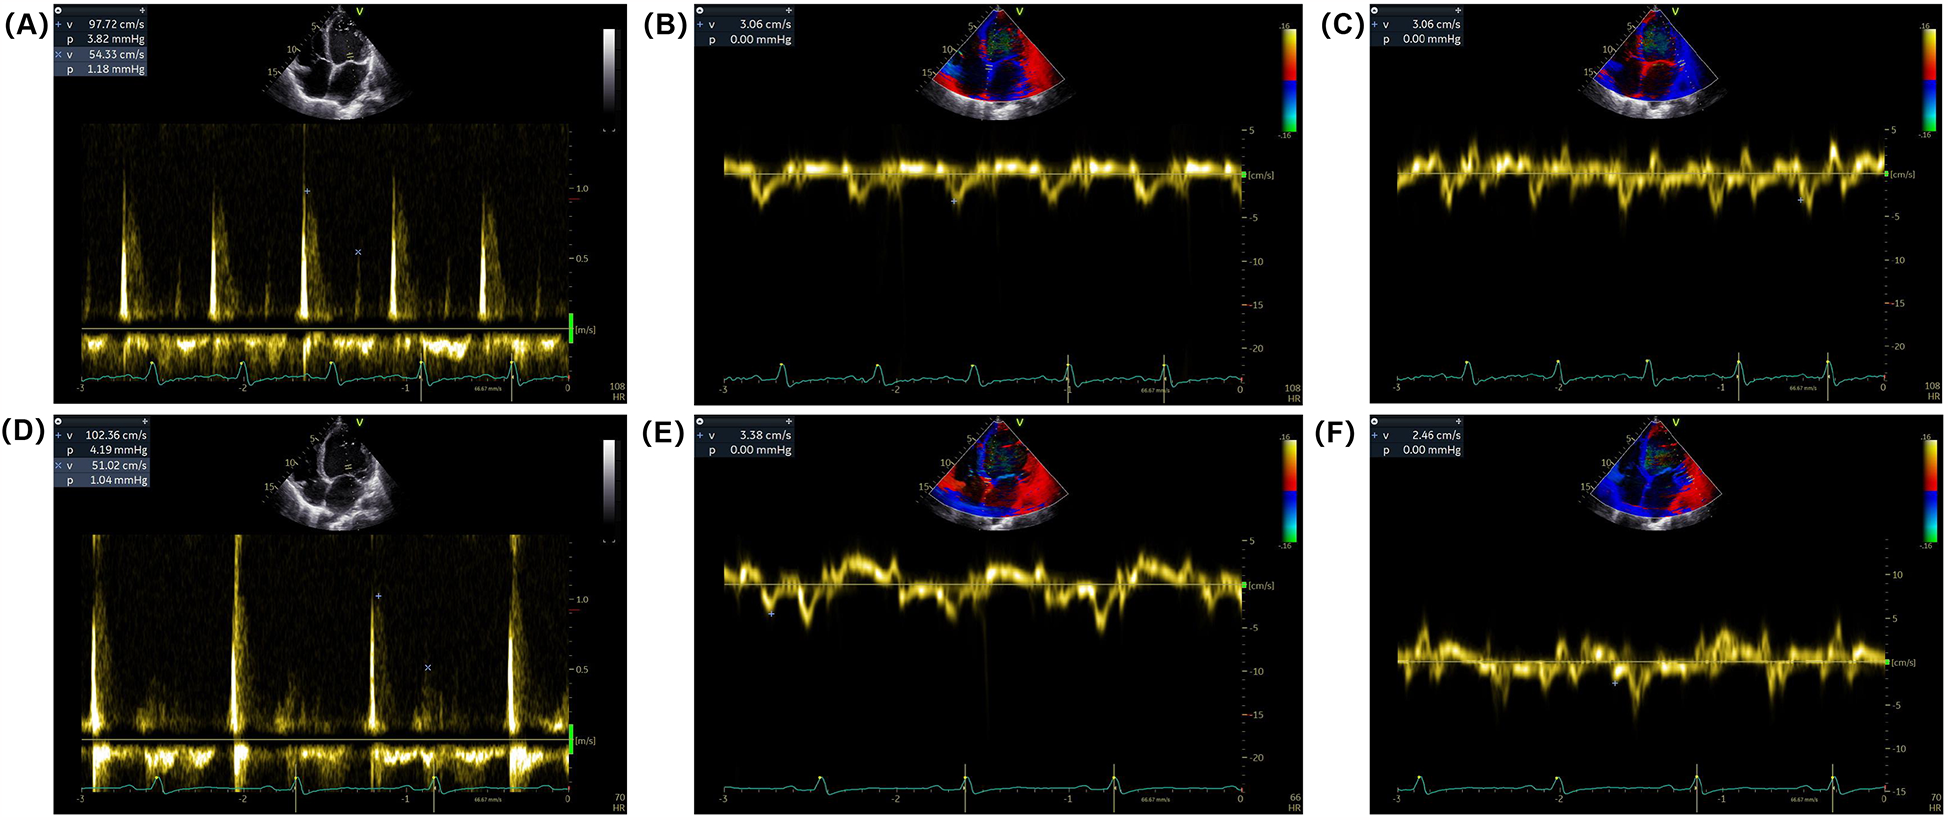

Electrocardiogram (ECG) on admission revealed sinus rhythm with a heart rate of 101 beats per minute and a QRS duration of 118 ms. 24-h Holter monitoring revealed sinus rhythm (average heart rate 89 beats per minute), 44 premature atrial contractions, and two episodes of short-duration atrial tachycardia. Continuous electrocardiogram and blood pressure monitoring device also did not show any evidence of atrial fibrillation. Echocardiography demonstrated global cardiac dilatation with both impaired left ventricular systolic and diastolic dysfunction, along with reduced right ventricular systolic. The LVEF was only 15% with an E/e’ ratio of 32.3, mtral inflow and tissue doppler imaging for diastolic function assessment are shown in Figures 1A–C. With moderate mitral regurgitation. Left ventricular wall motion was globally impaired. LV global longitudinal strain (GLS) was −3.3%. Although the patient was diagnosed with dilated cardiomyopathy (DCM), definitive supporting documentation was unavailable. Ancillary tests were performed to investigate the etiology of HF, with coronary angiography revealing no significant coronary artery abnormalities. Cardiac magnetic resonance imaging (MRI), both plain and contrast-enhanced, showed end-diastolic volume (EDV) of 288 ml, end-systolic volume (ESV) of 217 ml, stroke volume (SV) of 71 ml. MRI further revealed patchy fibrosis is observed in the mid-myocardial layer of the left ventricle and in the anterior and posterior walls at the junction of the left and right ventricles (Figure 2A). No fibrosis is noted in the interventricular septal myocardium, with the total fibrotic area comprising less than 50%. Based on these findings, the patient was diagnosed with DCM. Right heart catheterization (RHC) revealed a CO of 1.93 L/min, a mean pulmonary artery pressure (mPAP) of 42 mmHg, a pulmonary capillary wedge pressure (PCWP) of 30 mmHg, and a pulmonary vascular resistance of 6.21 WU.

Figure 1

Mitral inflow and tissue Doppler imaging for diastolic function assessment. (A) Pulsed-wave Doppler recordings of mitral inflow showing (E,A) waves at admission. (B,C) Tissue Doppler imaging of the mitral annulus showing early diastolic velocity (e’) at the septal and lateral annulus at admission. (D) Pulsed-wave Doppler recordings of mitral inflow showing (E,A) waves at discharge. (E,F) Tissue Doppler imaging of the mitral annulus showing early diastolic velocity (e’) at the septal and/or lateral annulus at discharge.

One week post-surgery, the incision site had healed without complications, and no surgical adverse events were reported, including pain on stimulation, tricuspid valve insufficiency, or stimulation-induced arrhythmia. The patient's dyspnea gradually improved, and his functional status was reclassified as NYHA functional class II at discharge. BP increased to 95–105/70 mmHg, and NT-proBNP levels decreased to 1,564 pg/ml. Follow-up echocardiography demonstrated an improvement in LVEF to 40%, with an E/e’ ratio of 35.1 (Figures 1D–F) and mild mitral regurgitation. LVGLS improved to −6.4%.